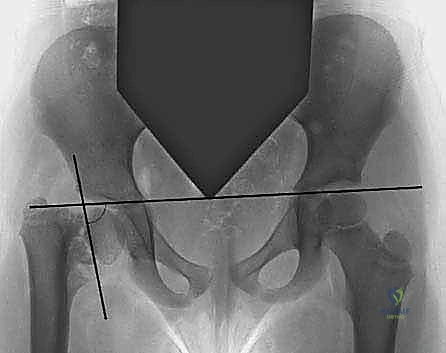

The natural history of developmental coxa vara dictates the indications for surgical intervention. The most critical prognostic indicator is the Hilgenreiner-epiphyseal angle (HEA), as extensively described by Weinstein et al. The HEA is measured on an anteroposterior (AP) radiograph of the pelvis as the angle subtended by Hilgenreiner’s line (a horizontal line connecting the bilateral triradiate cartilages) and a line drawn parallel to the proximal femoral physis.

Standard radiographic evaluation must include a standing AP pelvis and a frog-leg lateral view of the affected hip. The surgeon must meticulously calculate the preoperative HEA, the NSA, the ATD, and the degree of femoral retroversion.

The target postoperative HEA should be less than 38 degrees, with many authors advocating for a goal of 30 to 35 degrees to ensure a robust mechanical environment that prevents recurrence. The required angle of correction (the wedge to be resected or the angle of the opening wedge) is calculated by subtracting the desired postoperative HEA from the preoperative HEA. Concurrently, the NSA should be restored to at least 130 degrees.